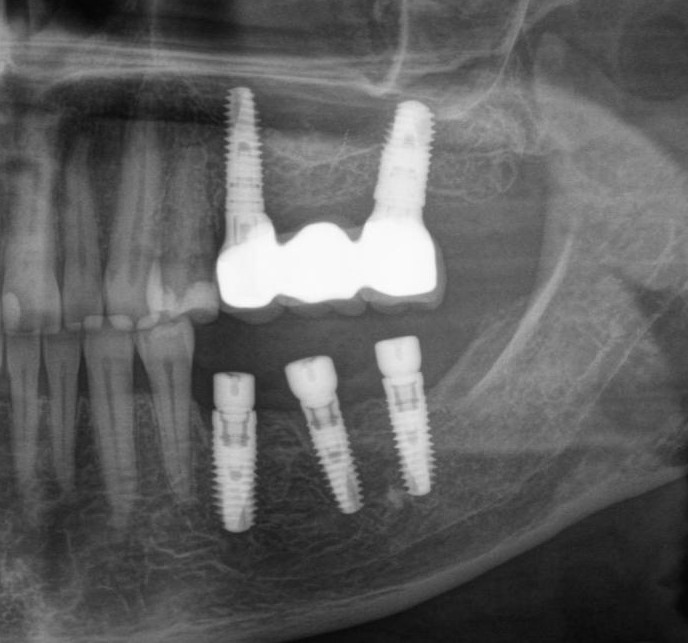

Исследование на рентгене после имплантации зубов

Раздел: Снимки-откровения